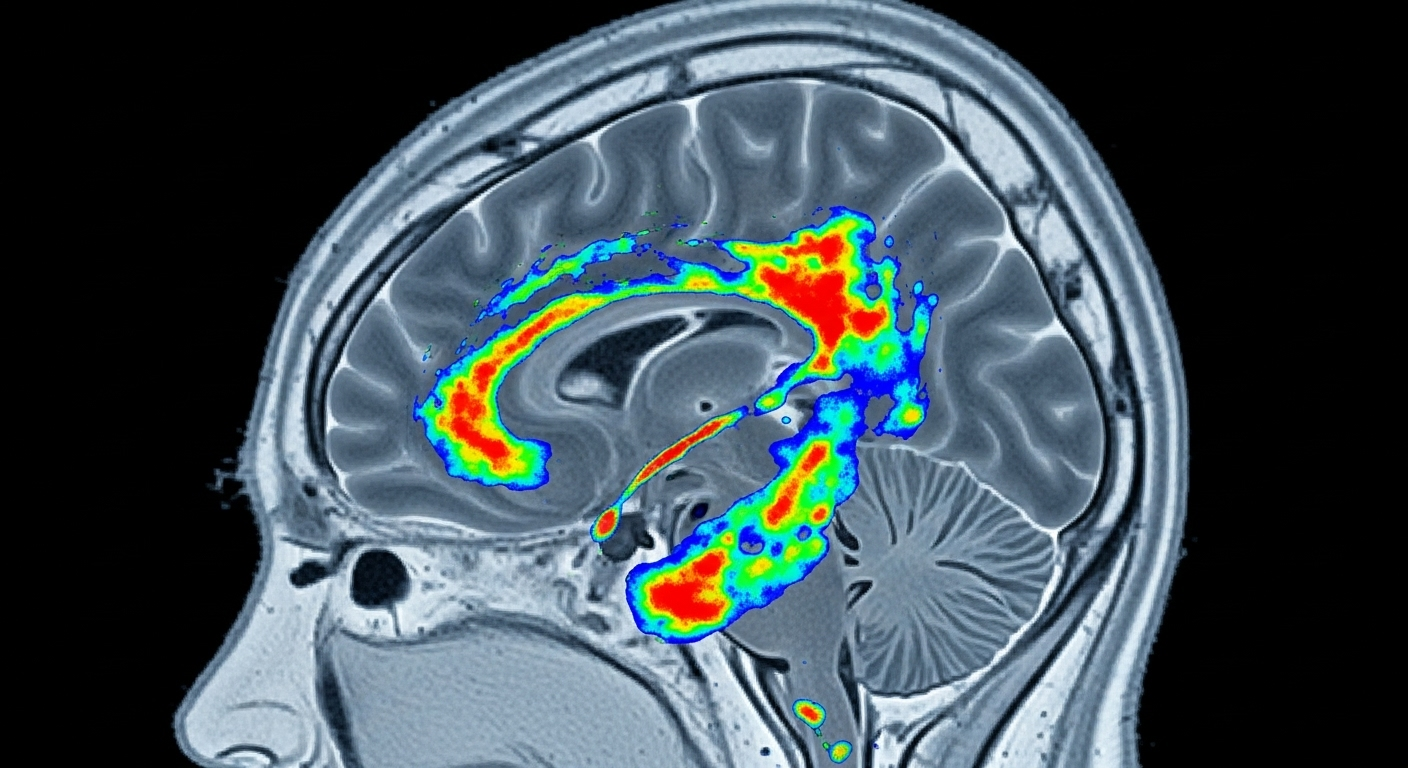

Pour l’instant, le diagnostic d’Alzheimer tombe souvent comme un couperet, bien après le début des hostilités. Lorsque les premiers trous de mémoire ou les troubles de l’orientation alertent l’entourage, les dégâts dans le cerveau sont hélas déjà bien installés. Les plaques amyloïdes et les enchevêtrements de protéine tau, les deux signatures de la maladie, ont eu des années pour faire leur œuvre en silence.

C’est précisément ce mur que la recherche est en train de faire tomber. Plusieurs équipes à travers le monde ont réussi à identifier dans le sang des biomarqueurs, des « signatures » chimiques, qui trahissent la présence des fameuses protéines anormales bien avant qu’elles ne provoquent des symptômes visibles. En somme, le sang devient un miroir de ce qui se passe dans le cerveau.